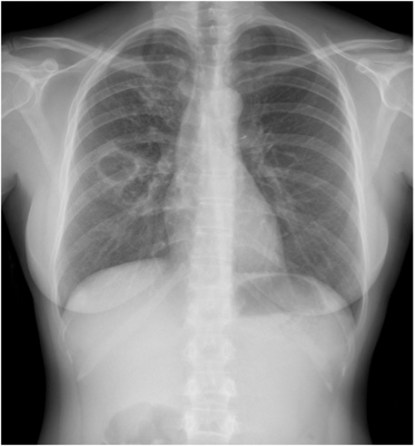

- Se observan múltiples nódulos en ambos hemitórax. Es el signo de la suelta de globos en relación con metástasis.

SUELTA DE GLOBOS:

Son múltiples nódulos pulmonares bien definidos de distribución bilateral y aleatoria y con diferentes tamaños. Sugieren metástasis pulmonares.

CASO: Disnea.

Hallazgos:

- Multiples nódulos disperos y bilaterales conformando un claro patrón en suelta de globos.